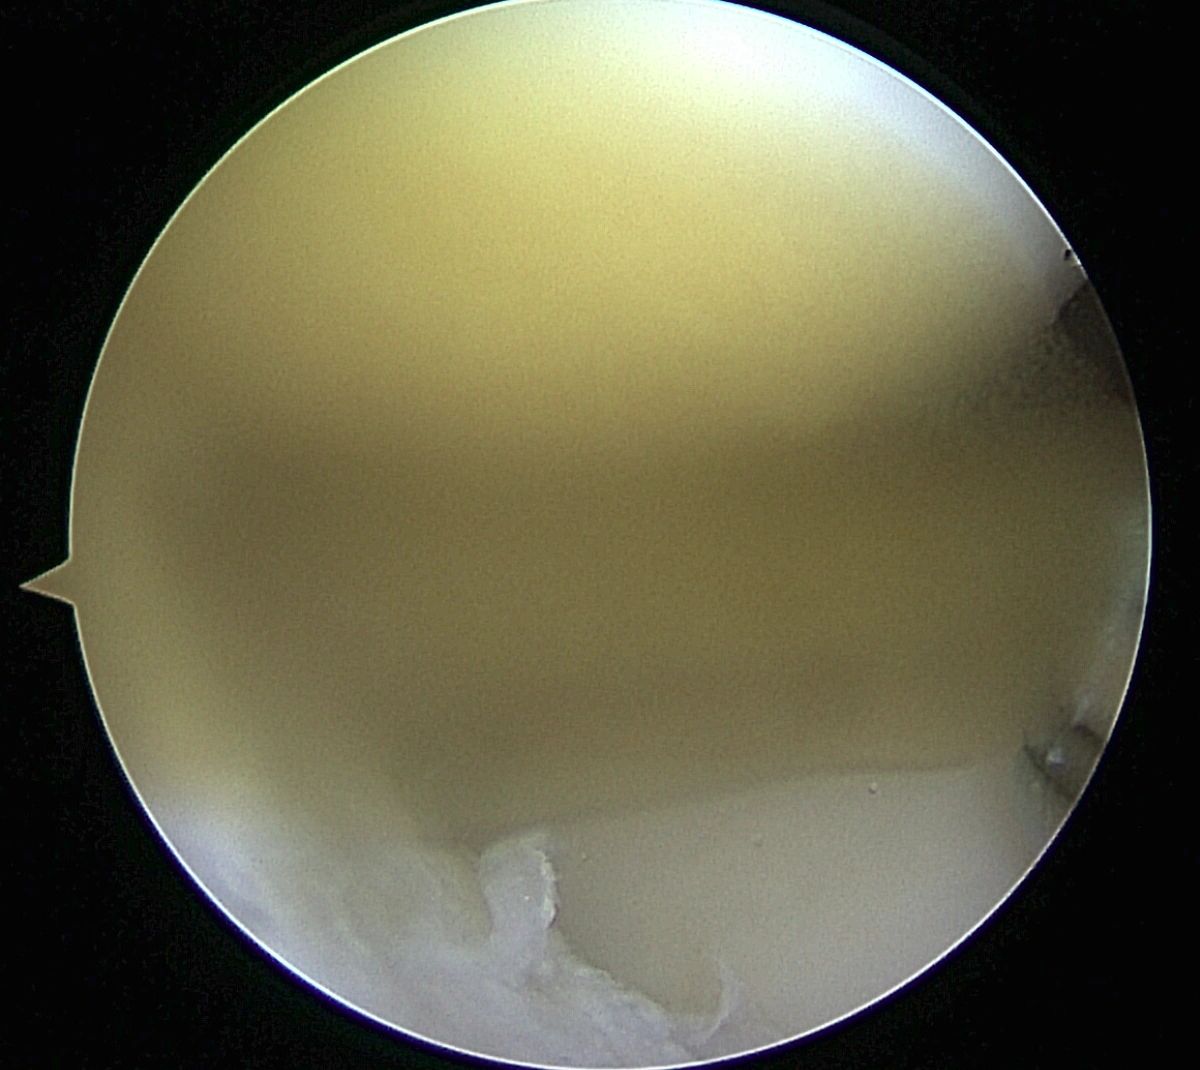

- Meniscus Surgery

- Meniscus Surgery 2